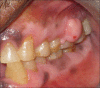

Peripheral ossifying fibroma (POF) is one of the inflammatory reactive hyperplasia of gingiva. It represents a separate clinical entity rather than a transitional form of pyogenic granuloma and shares unique clinical characteristics and diverse histopathological features. We present a case of POF in a 65-year-old male patient in the posterior maxillary gingiva, the clinical presentation of which differs from the usual presentation. Differential diagnosis and some interesting facts of POF are discussed.